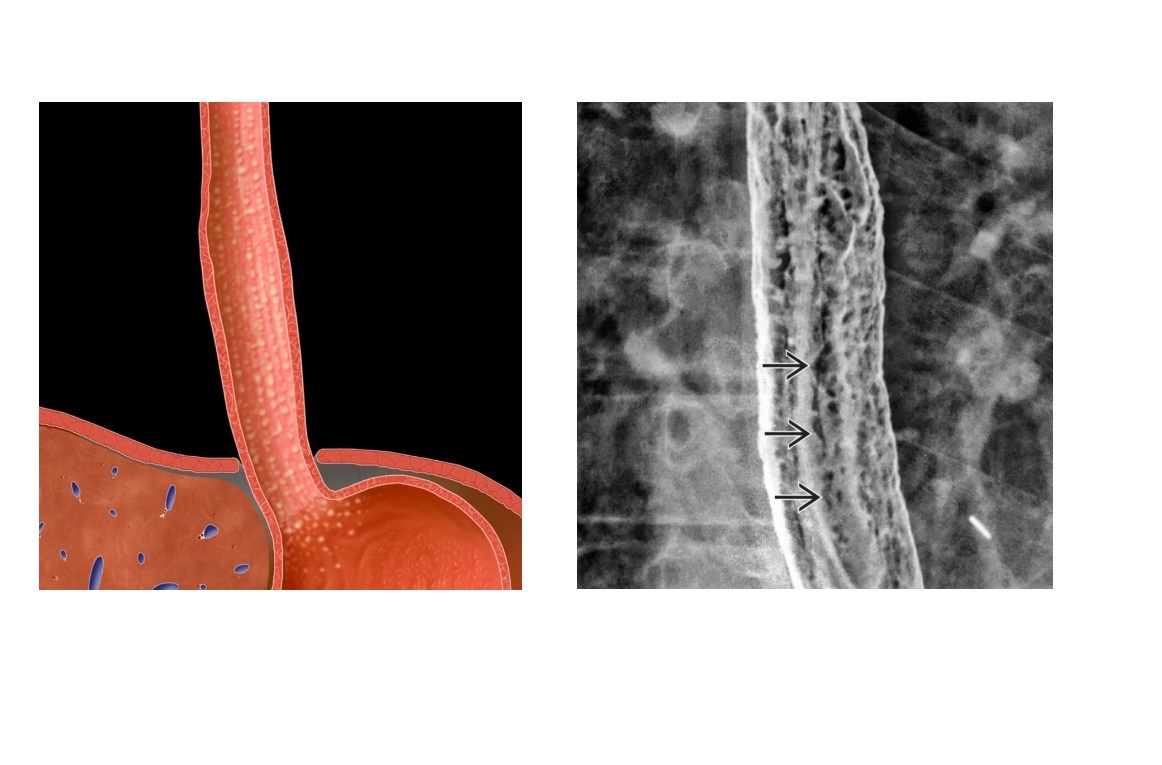

Mid oesophageal stricture, associated hiatal hernia and reflux?

A

Barretts

‘reticular muscosal pattern’